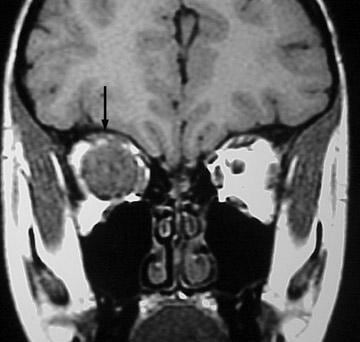

冠狀位t1加權(quán)MRI顯示一個(gè)大的眶內(nèi)腫塊(箭頭)以視神經(jīng)為中心。圖示:46歲男性軸向t2加權(quán)MRI顯示丘腦外側(cè)膝狀核腫塊,起因于患者已知視神經(jīng)膠質(zhì)瘤的連續(xù)延伸。雖然MRI可以發(fā)現(xiàn)視神經(jīng)的...